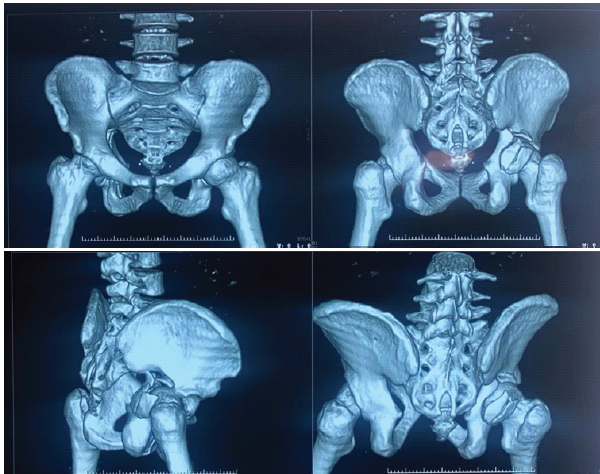

The 3-dimensional reconstructed computed tomography scans of the pelvis with both hip joints demonstrate a fracture involving the acetabulum, with disruption of the acetabular rim and articular surface on the affected side. There is a visible irregularity and discontinuity of the pelvic ring at the acetabular region, with extension of the fracture line into the surrounding pelvic bone. The femoral head appears seated within the acetabulum without gross dislocation, although subtle incongruity of the hip joint surface is noted, suggesting intra-articular involvement. The sacrum, sacroiliac joints, and contralateral hemipelvis appear intact, with no obvious widening or diastasis (Fig. 1 and 2).

Figure 1& 2: 3-dimensional reconstructed computed tomography scans of the pelvis with both hip joints.